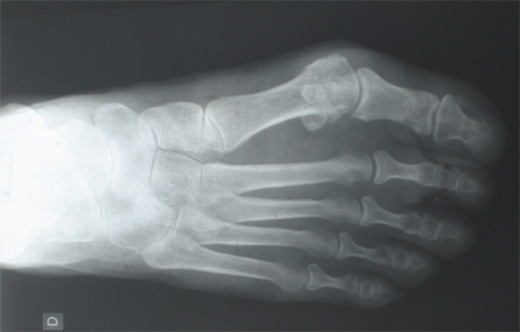

Quelques observations ont signalé l’intérêt potentiel de l’injection intraarticulaire d’acide hyaluronique dans l’arthrose de la métatarsophalangienne du gros orteil. Cette étude indépendante constitue le 1er essai contrôlé, randomisé ayant évalué l’efficacité potentielle de l’hylan G-F 20 dans l’hallux rigidus.

Il s’agit d’une étude réalisée en double aveugle (patients et évaluateurs) avec un suivi à 1, 3 et 6 mois. 1 mL soit d’hylan G-F 20, soit de sérum salé a été injecté sous contrôle scopique (par le même radiologue interventionnel). Une possible 2ème injection pouvait être effectuée en cas de non amélioration